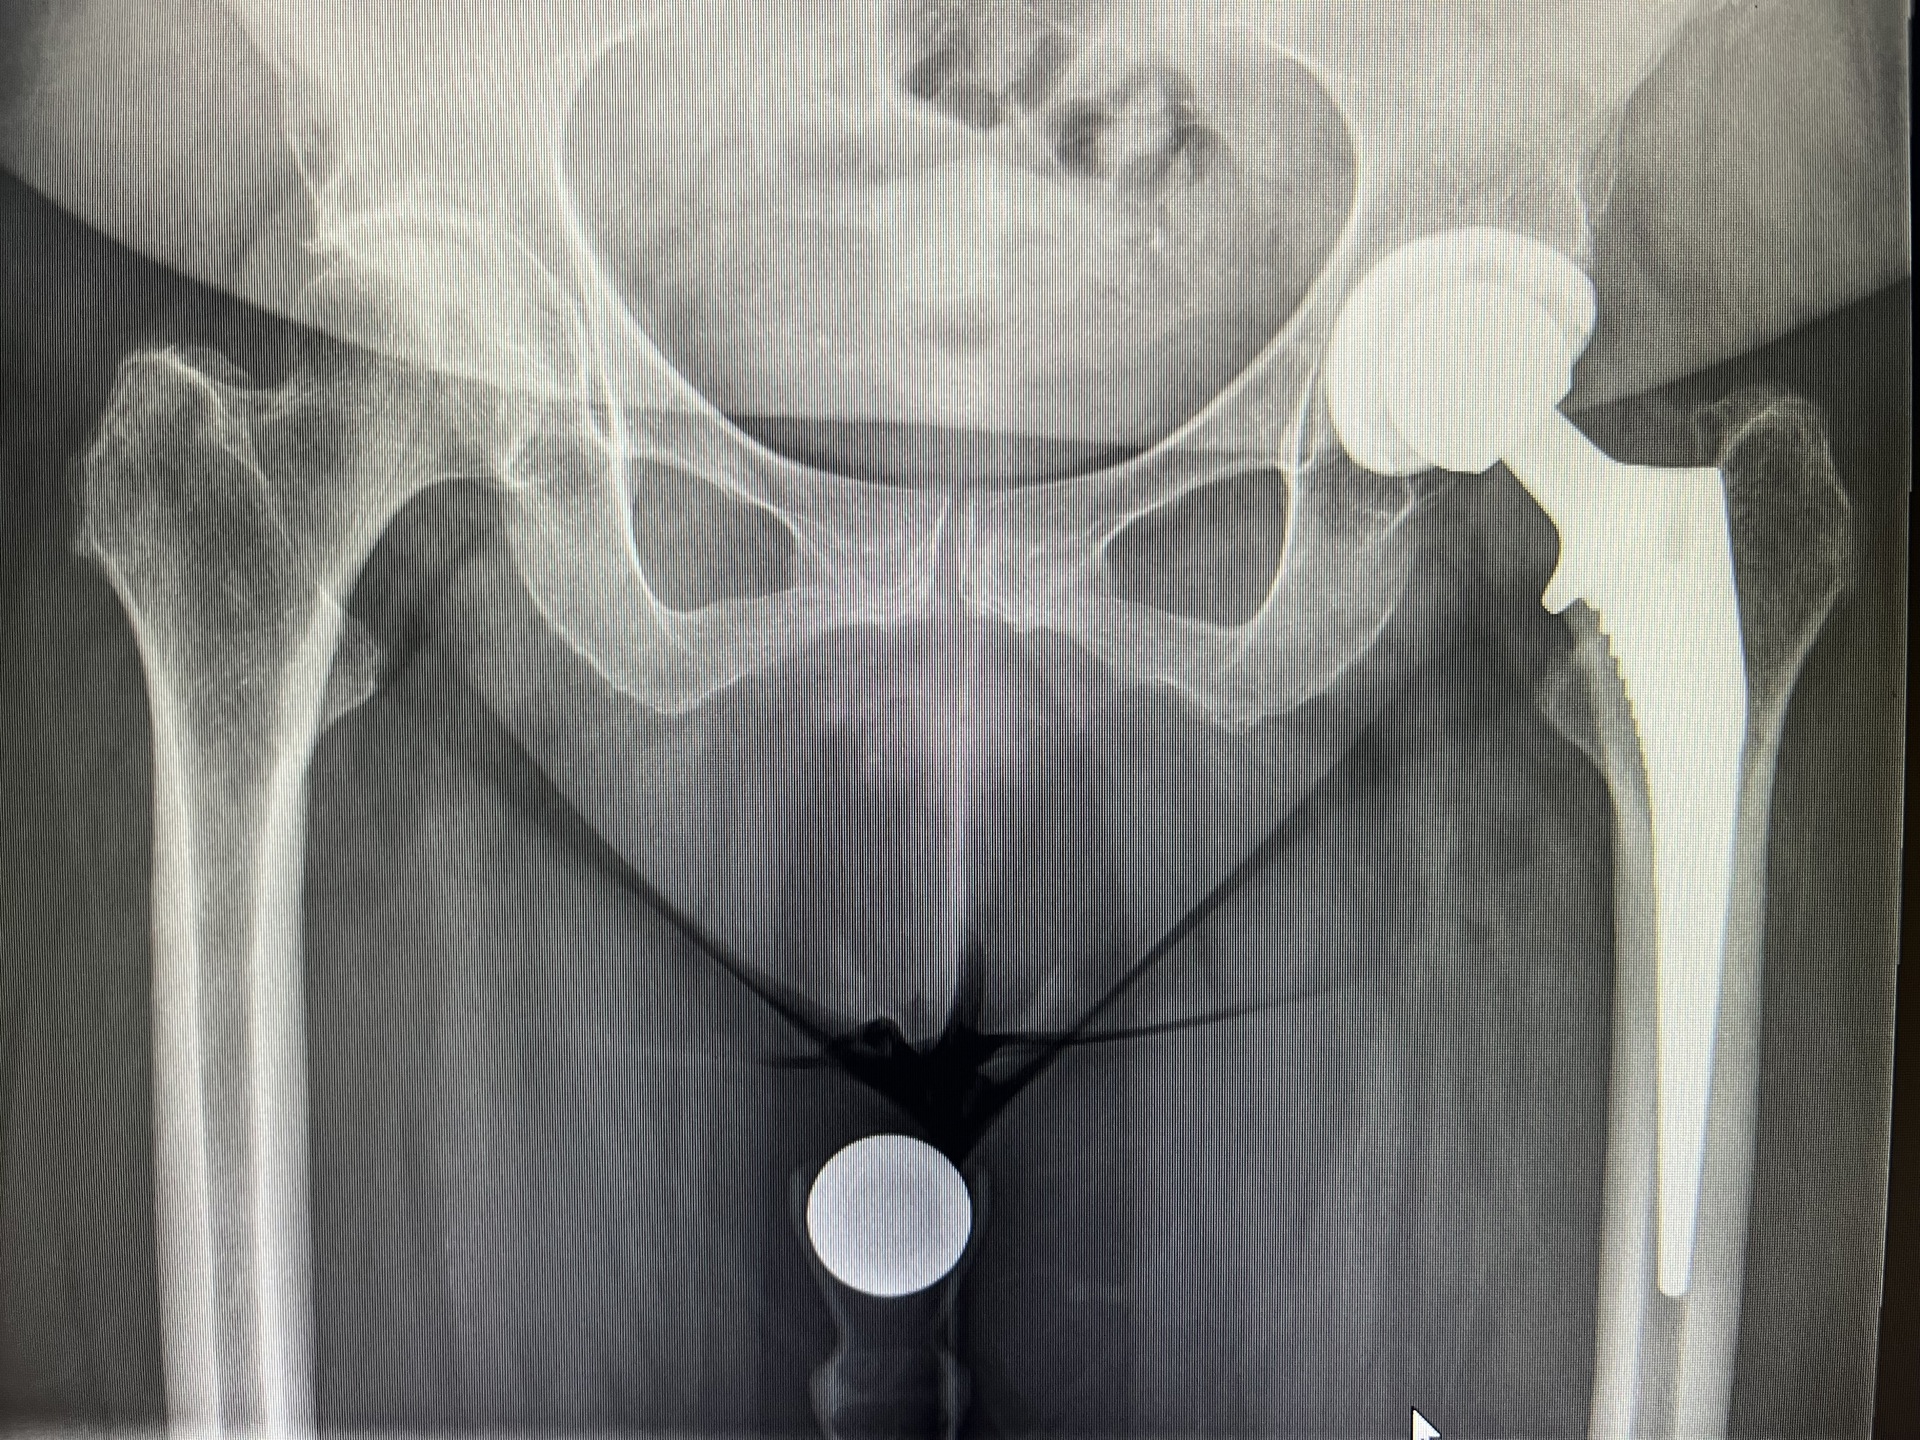

• Endoprothetik des Hüft- und Kniegelenkes

• Zertifizierter Hauptoperateur des Endoprothetikzentrums der Asklepios Klink Lich